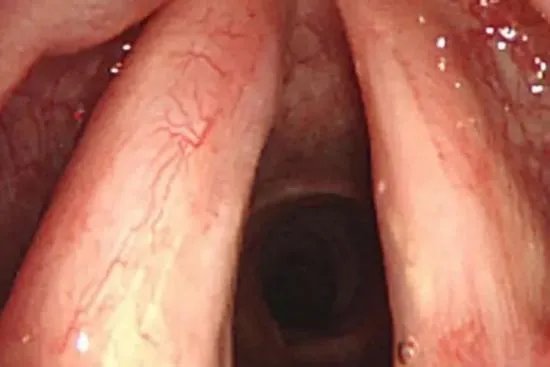

概述声带位于喉腔中部,由声韧带连同声带肌及覆盖于其表面的喉黏膜一起构成。声带是人类发声的主要结构,成年男子声带长而宽,女子声带短而狭。结构声带位于喉腔中部,左右对称,声韧带连同声带肌及覆盖于其表面的喉黏膜一起构成声带,其较薄的游离缘为膜部,基部为软骨部。膜部覆有复层扁平上皮,固有层较厚,大量弹性纤维与表面平行排列,形成了致密板状结构,称声韧带。固有层下方的骨骼肌为声带肌。

作用声带是人类发声的主要结构,声带振动主要发生在膜部。发声时,两侧声带拉紧、声门裂缩小,甚至关闭,从气管和肺冲出的气流不断冲击声带,引起振动而发声,在喉内肌肉协调作用的支配下,使声门裂受到有规律性的控制。故声带的长短、松紧和声门裂的大小,均能影响声调高低。成年男子声带长而宽,女子声带短而狭,所以女子比男子声调高。青少年14岁开始变音,一般要持续半年左右。